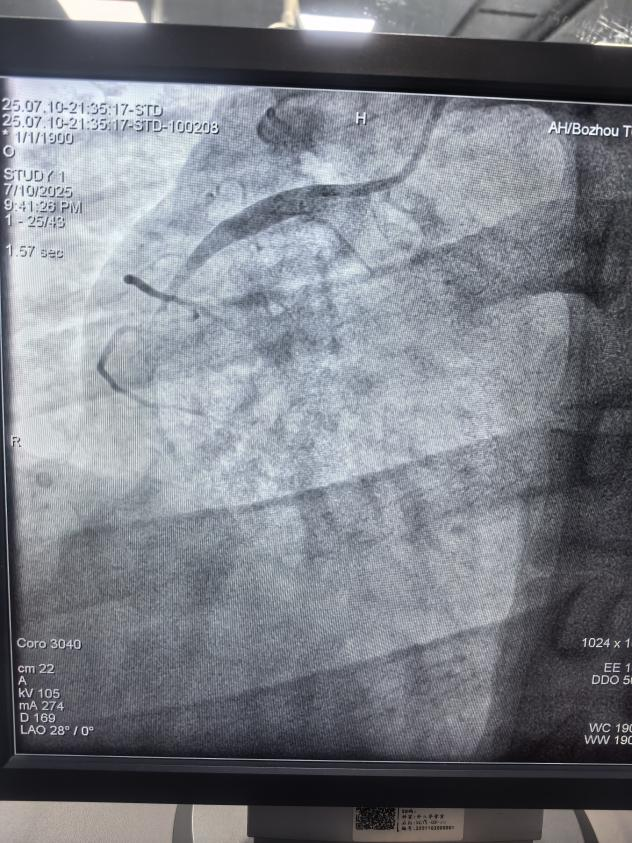

患者馮先生身高170cm,體重95kg,體型較為肥胖,平時(shí)作息不規(guī)律,長期抽煙、飲酒、熬夜,當(dāng)天突發(fā)心前區(qū)疼痛持續(xù)不能緩解,伴有大汗淋漓、煩躁不安,通過呼叫120救護(hù)車送至我院胸痛中心。心血管病科二病區(qū)介入醫(yī)生給他做了急診冠脈造影檢查,顯示右冠狀動(dòng)脈近段急性完全閉塞。經(jīng)過手術(shù)醫(yī)生積極有序的救治,順利開通閉塞血管后,在血管內(nèi)超聲指引下精確植入一枚藥物洗脫支架,植入后血流恢復(fù)良好,馮先生癥狀明顯改善,生命體征逐漸平穩(wěn)。術(shù)后身體恢復(fù)良好,于7月20日順利出院。

右冠急性閉塞